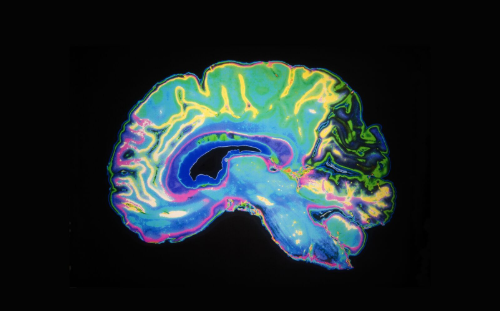

Neurological and Behavioral Perspectives

Eye Movement Desensitization and Reprocessing (EMDR) therapy has shown promise in addressing the psychological roots of nail biting and skin picking. Originally developed for PTSD, EMDR helps individuals process distressing memories and reframe negative thought patterns. During therapy, bilateral stimulation, such as guided eye movements, aids in reducing the emotional intensity of traumatic experiences.

In the context of BFRBs, EMDR can help identify and address underlying triggers, such as unresolved grief, anxiety, or anger. By desensitizing these emotional pain points, individuals can break free from the compulsive urge to engage in nail biting or skin picking. EMDR also fosters emotional regulation, enabling individuals to adopt healthier coping mechanisms.